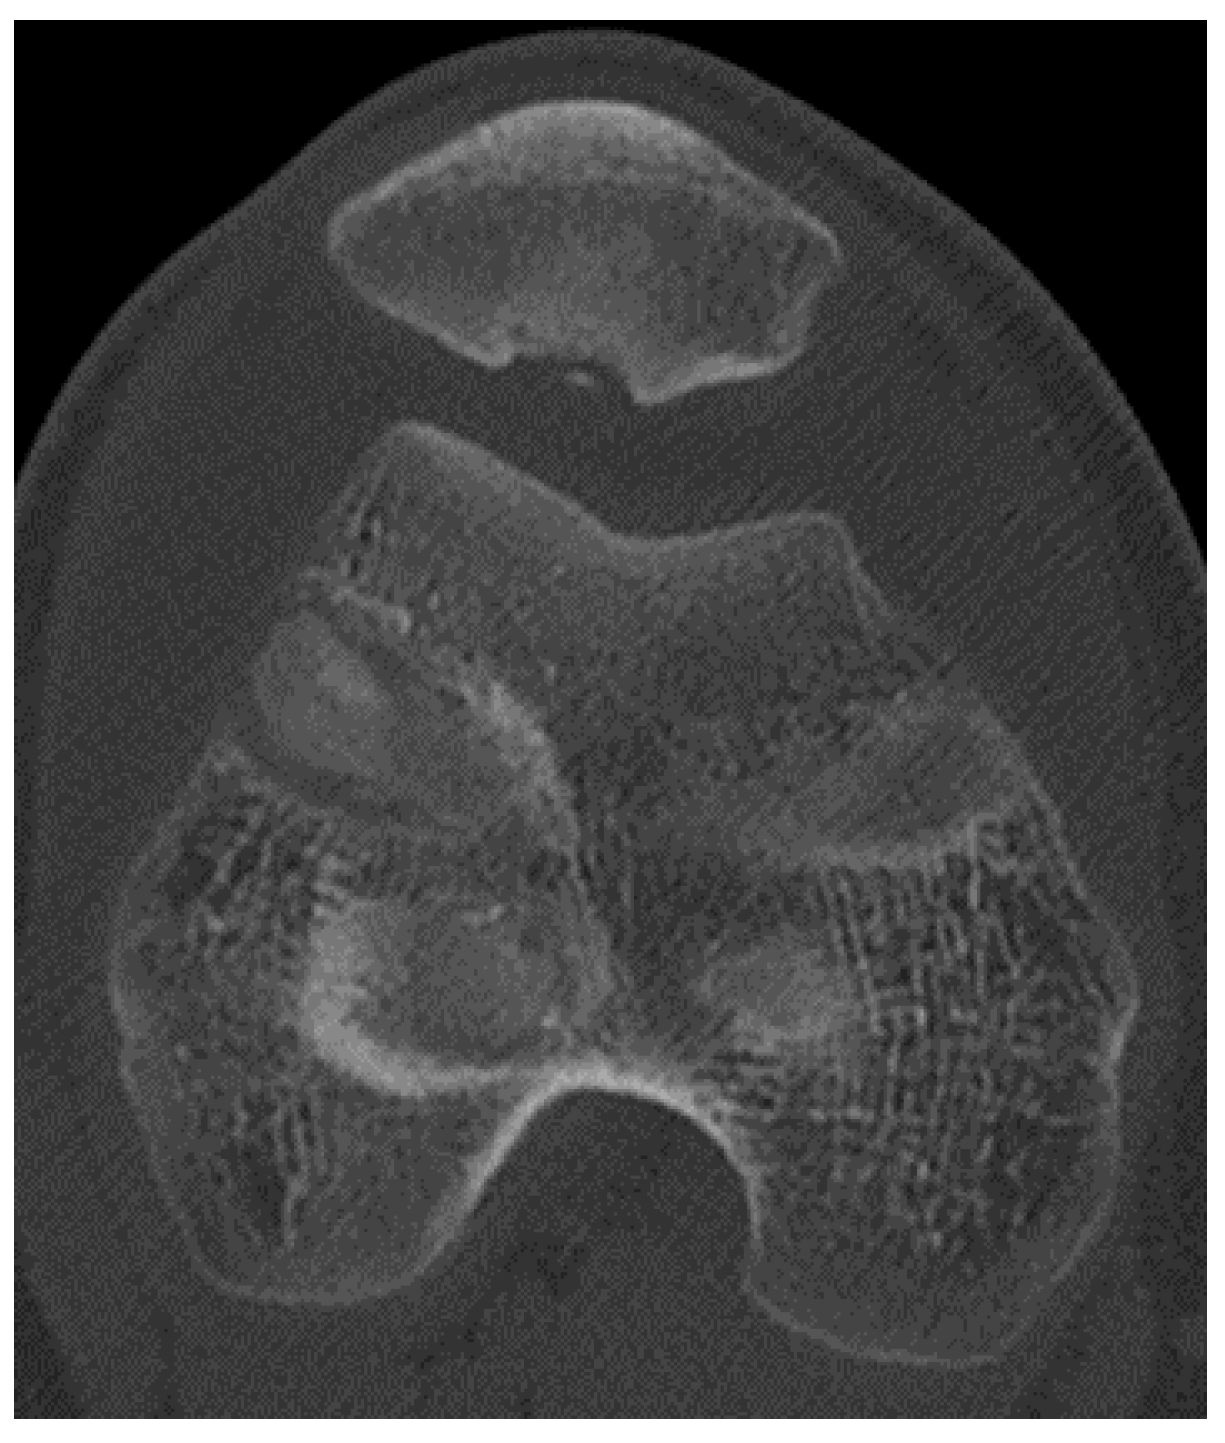

In the Emergency Department, all patients underwent first-level instrumental examinations: a first line X-ray examination was performed, and those patients with a suspected fracture or osteochondral detachment on the X-ray imaging were further on evaluated with CT scan diagnostics (Figure 1).

3.2. Computer Tomography (CT)

Scans throughout our in-depth study, instances were noted where patients’ X-rays exhibited ambiguous images, suggestive of fractures or osteochondral detachments. In such scenarios, a CT scan became imperative to enrich the diagnostic clarity to better understand the overall picture. CT scans provide an efficient means to measure the TT-TG distance, an integral metric when evaluating and managing patellar dislocations. To discern this, a tangent line is drawn connecting the posterior borders of both femoral condyles. Subsequently, two perpendicular lines are marked: one (A) from the tibial tubercle’s apex, and the other (B) from the trochlear groove’s deepest point. The spacing between lines A and B is the TT-TG distance. A standard measurement stays below 20 mm, with anything surpassing this limit deemed anomalous. Beyond this, CT scans adeptly outline the presence, depth, and extent of osteochondral fractures, equipping medical professionals with insights to strategize potential most suitable surgical interventions [12,13].

Figure 1. CT scan image of an osteochondral lesion of the patella.